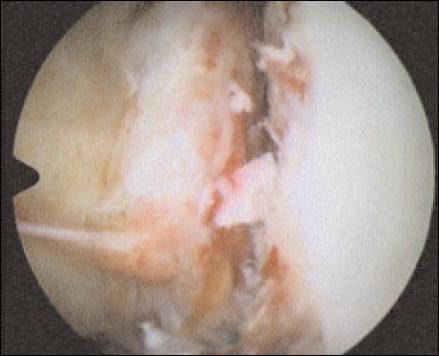

Comenzamos la evaluación artroscópica: identificamos y clasificamos la lesión labrocapsular, efectuamos la medición de la superficie glenoidea para constatar deficit óseos, buscamos y evaluamos la lesión de Hill-Sachs o su equivalente y exploramos completamente la cavidad articular. Realizamos la liberación de las estructuras blandas para permitir su reducción en el sitio deseado efectuando un debridamiento de la cápsula y sus ligamentos para su reinserción en el reborde glenoideo anterior previamente abrasionado (Fig. 2).

Figura 2: lesion tipo III